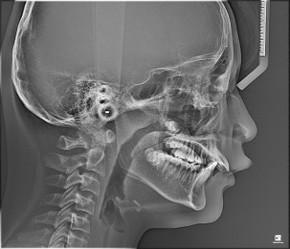

오늘은 심한 무턱 증상으로 윗 치아 쪽이 많이 튀어나와 보이던 성장기 환자분을 소개시켜드리려 합니다.

환자분도 치료 결과에 너무 신기해 하셨지만 무엇보다 어머님께서 너무나 만족하셔서 저희도 뿌듯했던 케이스입니다. |